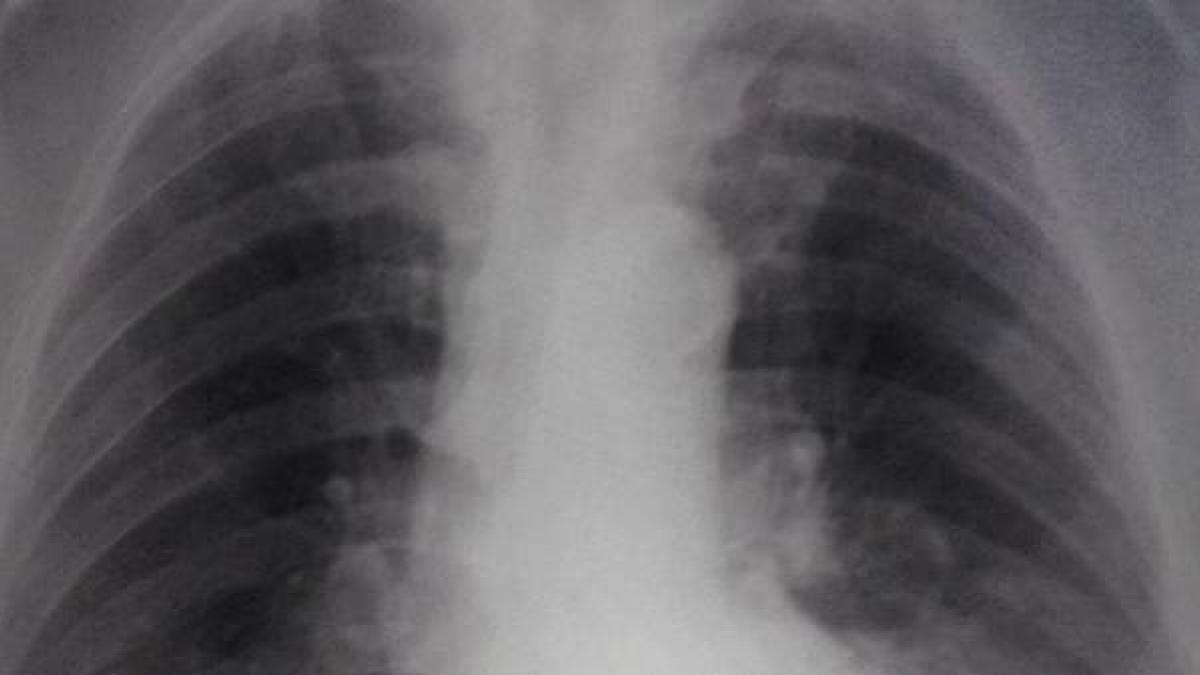

Por tanto, los pulmones acumulan líquido y las concentraciones de oxígeno en la sangre son demasiado bajas, por lo que requiere atención médica urgente. Este problema afecta a menudo a personas que presentan patologías respiratorias previas, aunque también en personas sanas. Además, es una afección que puede afectar a recién nacidos y niños.

Las causas de este síndrome no están totalmente definidas, pero puede ser causado por una lesión directa o indirecta a los pulmones. De hecho, «cualquier enfermedad o alteración que cause daño pulmonar puede producir un síndrome de dificultad respiratoria aguda». Así, un gran porcentaje de personas lo desarrollan «a consecuencia de una grave y extensa infección (sepsis) o neumonía», indican en MSD Manuals.

De esta manera, la gravedad de esta afección dependerá del nivel de oxígeno en sangre y la cantidad que necesita el organismo, por lo que puede ser leve, moderada o grave. Las causas que pueden provocar este síndrome pueden ser:

En algunos casos, la disminución de las cantidades de óxigeno en sangre provocadas por este síndrome, junto con la liberación de citoquinas, puede conllevar a una inflamación de otros órganos y provocar un fallo multiorgánico.

Los síntomas varían dependiendo de la gravedad de la afección y si existe una patología pulmonar o cardíaca previa. Por lo general, las personas con síndrome de dificultad respiratoria aguda presentan uno o varios síntomas como: falta de aire (disnea), presión arterial baja, dificultad para respirar o respiración y ritmo cardíaco acelerado, fatiga, cansancio extremo o confusión.